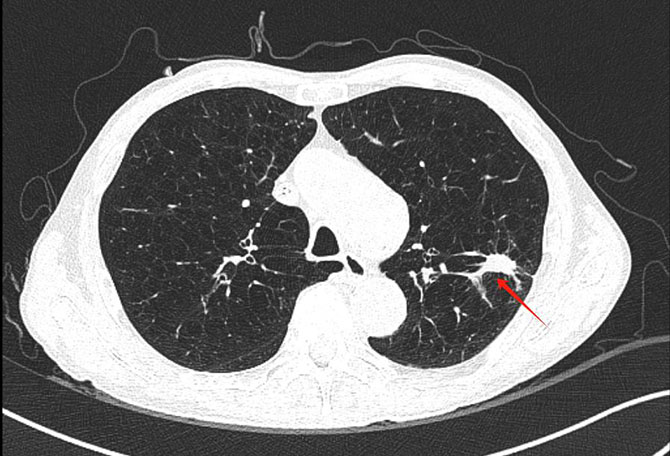

停止抗肿瘤治疗3月后复查,何叔的CT发现左上肺新出现转移灶,需要及时处理。然而,患多种疾病的何叔心肺功能较差,外科手术或经皮消融术风险极高。

患者术前CT